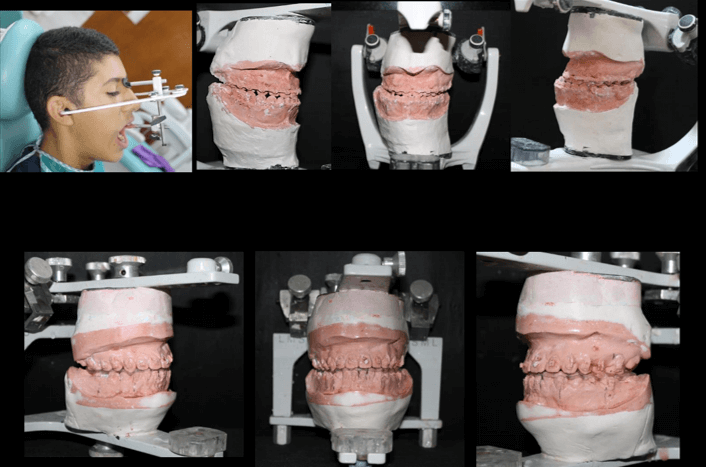

Montaje en Articulador Semiajustable y Cirugía de Modelo